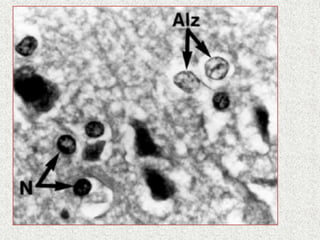

“Alzheimer type II astrocytosis”

– Pale, enlarged nuclei

– characterisic of HE

Increase Permeability ofBlood-Brain Barrier • Astrocyte (glial cell) volume is controlled by intracellular organic osmolyte which is glutamine • Increase glutamine levels in the brain result in increase volume of fluid within astrocytes resulting in cerebral edema (enlarged glial cells) • Neurological impairment “Alzheimer type II astrocytosis” – Pale, enlarged nuclei – characterisic of HE